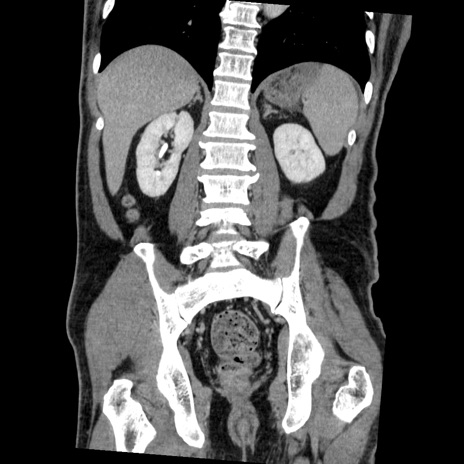

横断像

【症例】50歳代男性

【主訴】腹痛

【現病歴】AVMからの被殻出血のため回復期リハ病棟入院中。 本日午後3時頃急に下腹部痛が出現した。

【既往歴】AVM、被殻出血、虫垂炎、高血圧

【身体所見】意識晴明、左半身不全麻痺、会話の理解は良好、36.5°C、腹部:膨隆、全体に板状硬、下腹部正中に圧痛点あり、反跳痛-、筋性防御不明、右下腹部にope scar

【データ】WBC 9400、CRP 0.06